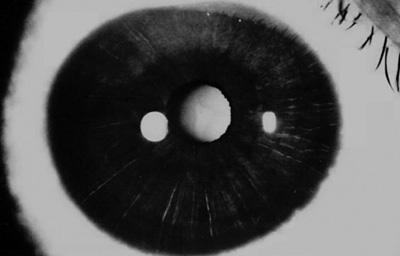

Paciente masculino de 18 años, estudiante a quien ( 10) dias antes , picadura de “avispa negra” en el Ojo Derecho en Sasaima, tratado con antibióticos y antiin amatorios corticoides, y Midriacyl 3 al día. Al examen: Edema corneal, Nubécula superior a las 12, PK ́s en Endotelio, Tono digital aumentado, Iris con atro as estromales, pupila en midriasis. AVsc. 0.33 , TO: 20 - Ojo Izquierdo sin alteraciones, (Foto No 3)

Foto 3 - Picadura en su estado inicial

El tratamiento es mantenido sin cambios durante el primer mes con controles periódicos cada 6 días. En el segundo mes, la córnea es trasparente con leucoma superior, Tono ocular digital blando; se reduce la medicación manteniendo el Pred F cada 2 horas, Timolol cada 12 horas y Tobrex 2 gotas al día.

Al tercer mes córnea trasparente con despigmentación del estroma iridiano, No hay transiluminación en el Iris. TO: 13 aplanático de Goldman, se inicia catarata subcapsular anterior.

A los 6 meses se realiza angiografía del Iris que muestra en las fases tardías la existencia de exudación en el estroma superior, pupila de 3.0mm normoreactiva (Foto No 6 y 7), y se formula Pred F nuevamente cada 2 horas durante 1 mes con reducción progresiva hasta el siguiente control.

A los 18 meses se realiza una segunda angiografía del Iris,(Foto No 8 ) mostrando ausencia de exudación; la córnea es trasparente con leucoma tenue superior, despigmentación del estroma iridiano en 360o con pupila de 3.0mm normoreactiva (Foto No 9), opacidad subcapsular anterior en el cristalino y Refracción: Plano ( -1.25 x 180a) 0.80. Se sugiere mantener Pred F 1 gota cada 5 días.

Foto 7 Foto del OD a los 6 meses

mostrando edema a las 12 y despigmentación del Iris en 360o

Foto 9 Foto a los 18 meses post tratamiento

Ultimo control a los 28 meses del accidente, con ojo OD tranquilo TO: 10, córnea trasparente con leucoma superior residual, despigmentación del Iris en 300o con pupila normoreactiva y opacidad anterior en el cristalino. Agudeza Visual mejor corregida 0.80